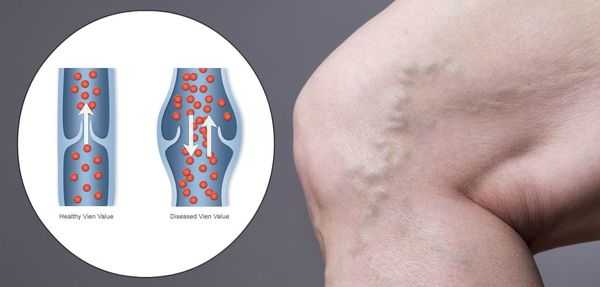

Патогенез ХВН очень специфичен. У здорового человека отток крови происходит через глубокие вены голени. Благодаря совместной работе постоянно сокращающейся и расслабляющейся скелетной мускулатуры и клапанного аппарата кровь направляется к сердцу, где она насыщается кислородом. В процессе этой работы гладкая скелетная мускулатура усиливает давление на вены, а клапанная система, которая состоит из смыкающихся створок, не позволяет крови поддастся силе тяжести.

Из-за длительно существующих факторов риска возникает венозная гипертензия, происходит расширение и выпячивание стенки вен. Створки клапанов расходятся и не могут препятствовать патологическому оттоку крови. Увеличенный объём крови сильнее давит на стенку вены, поэтому вена расширяется. Если не начать лечение, вена продолжит расширяться. Стенки сосудов начнут стремительно терять свою эластичность, их проницаемость увеличится. Через стенки в окружающие ткани будут выходить элементы крови, плазма. Таким образом возникает отёк тканей, что еще больше обедняет их кислородом. В тканях накапливаются свободные радикалы, медиаторы воспаления, запускается механизм активации лейкоцитов. Это нарушает питание и обмен веществ тканей. Конечным итогом становится образование «венозных» трофических язв, что существенно снижает качество жизни пациента. [4] [6]

Работа венозных клапанов в норме и при варикозном расширении вен